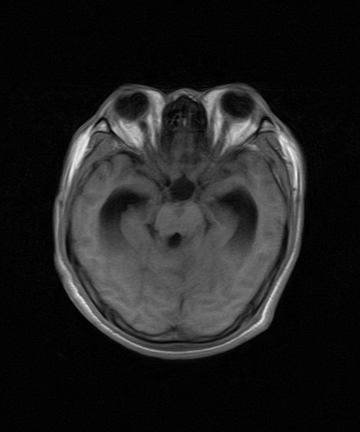

标题: MRI2064:少见病例。男性52,视力下降多年。 [打印本页]

标题: MRI2064:少见病例。男性52,视力下降多年。

四脑室区见混杂信号占位影,脑室系统扩张明显,临近结构显著受压称位,患者52岁,多考虑室管膜瘤可能性大

考虑第四脑室室管膜瘤并阻塞性脑积水。

应该是来源于小脑蚓部的占位,如血管母细瘤或星形细胞瘤

小脑蚓部胶质脑膜瘤突入四脑室;肿瘤内见血管流空信号和钙化信号.

比较典型的脉络丛乳头状瘤并脑积水,鉴别小脑蚓部血管母细胞瘤。